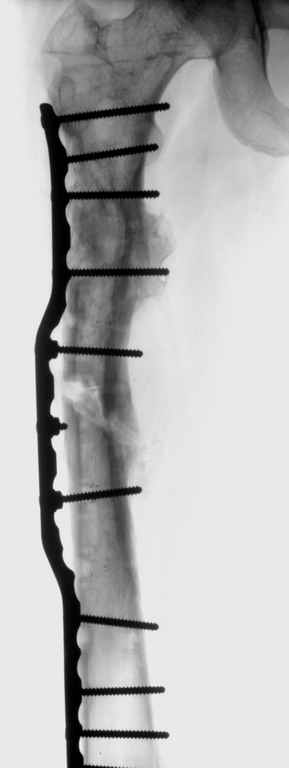

Leonid Pollyak 02 Январь 2005, 22:42

В ноябре этого года я обращался с просьбой о помощи в выборе тактики лечения больной с деформацией бедра на почве фиброзной дисплазии. Были получены интересные и очень полезные советы по операции.

Хотелось бы показать, что получилось в результате.

Операция выполнялась с помощью А.Н.Челнокова. Очень понравилась технология выполнения блокируемого остеосинтеза с использованием спицевого дистрактора, модифицированный гвоздь с латерализованным проксимальным отделом и возможностью многовинтовой фиксации проксимального и дистального участков бедра.